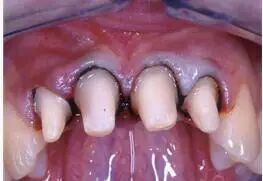

圖4 用排齦線排齦后局部粘膜發(fā)白、肩臺清晰